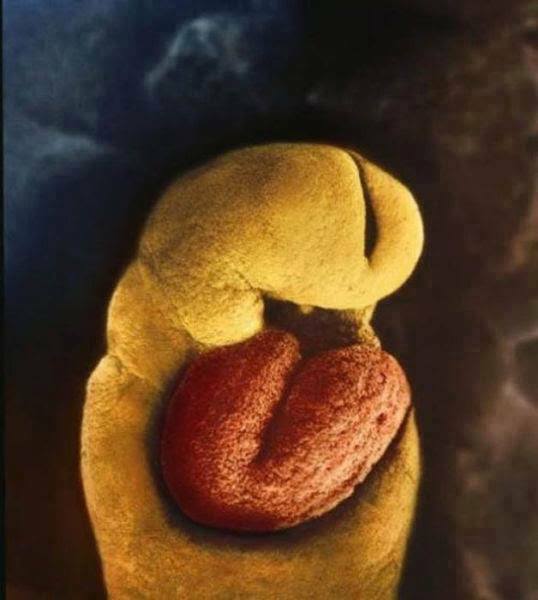

8.胚胎開始發育腦部,這時候胚胎的形狀看起來真的好奇特,完全想不到它竟然會進化成寶寶啊!

9.懷孕24天, 胚胎還沒有發育出任何骨骼,只有一顆從受孕第18天起就開始跳動的心臟。